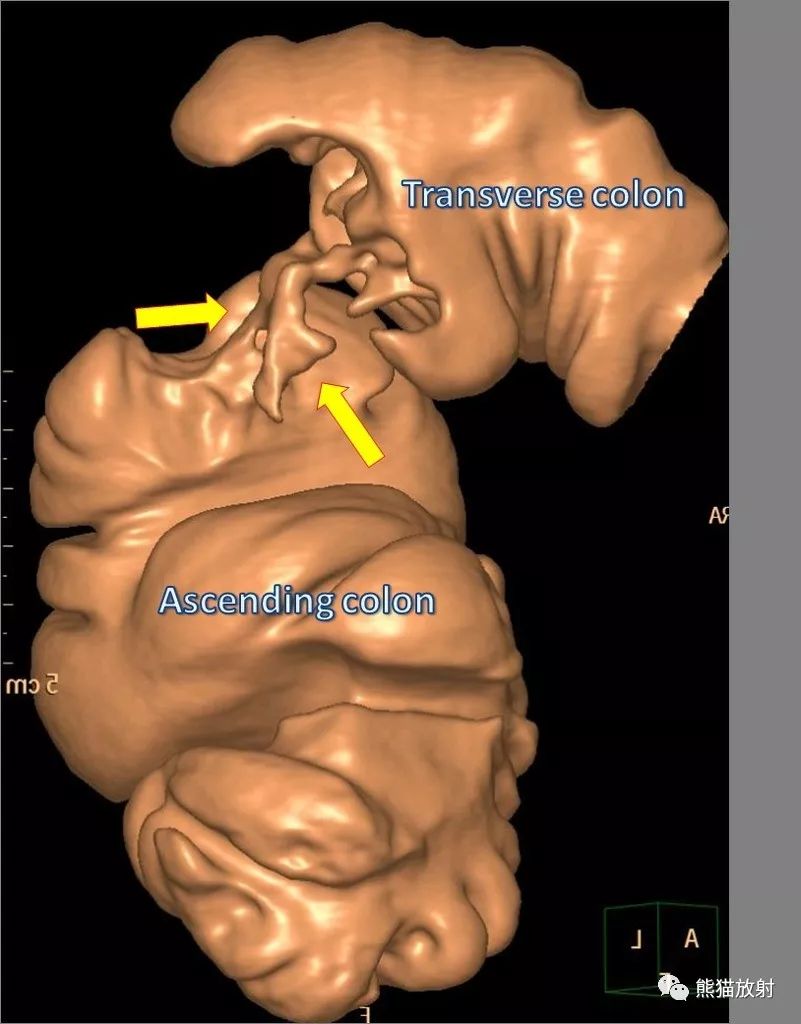

肝曲结肠癌CT表现(MPR、VR):

肿瘤沿肠壁环周浸润超过肠管周径的2/3时,可产生本征象。其两端为环堤形成的隆起边界,中央的管腔狭窄段为癌性溃疡所形成的癌性隧道。

在钡剂灌肠造影中环状结直肠癌表现为肠管的圆周状狭窄,与相对正常的肠段交界部界限清楚,形态僵硬,狭窄长度一般以3~6cm为多见,并有黏膜破坏,边缘呈大陆架状、悬垂状。